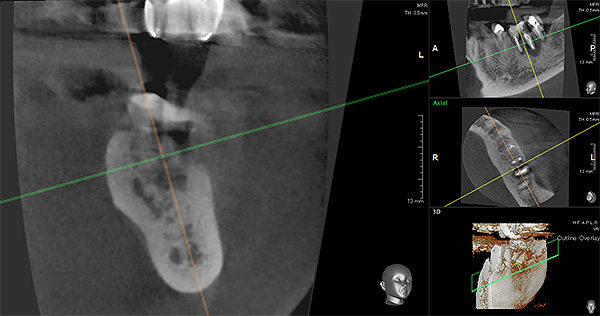

いなば歯科では歯科用CTやマイクロスコープ(歯科用顕微鏡)を使用し「出来るだけ自分の歯を残していく治療」を行っております。